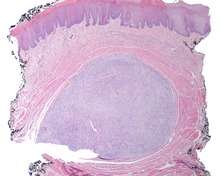

A very low power hematoxylin and eosin stained slide of an ectomesenchymal chondromyxoid tumor. Note the well demarcated tumor, separate from the overlying, intact squamous mucosa.

The overlying surface epithelium is intact and unconnected to the well circumscribed, but unencapsulated ectomesenchymal chondromyxoid tumor of the tongue. There are numerous skeletal muscle bundles at the periphery of the tumor. - The tumor is made up of small round, oval, spindle, or stellate cells that have a very monotonous appearance. There are small dark nuclei with variably amounts of light to basophilic cytoplasm.[1][5][7]